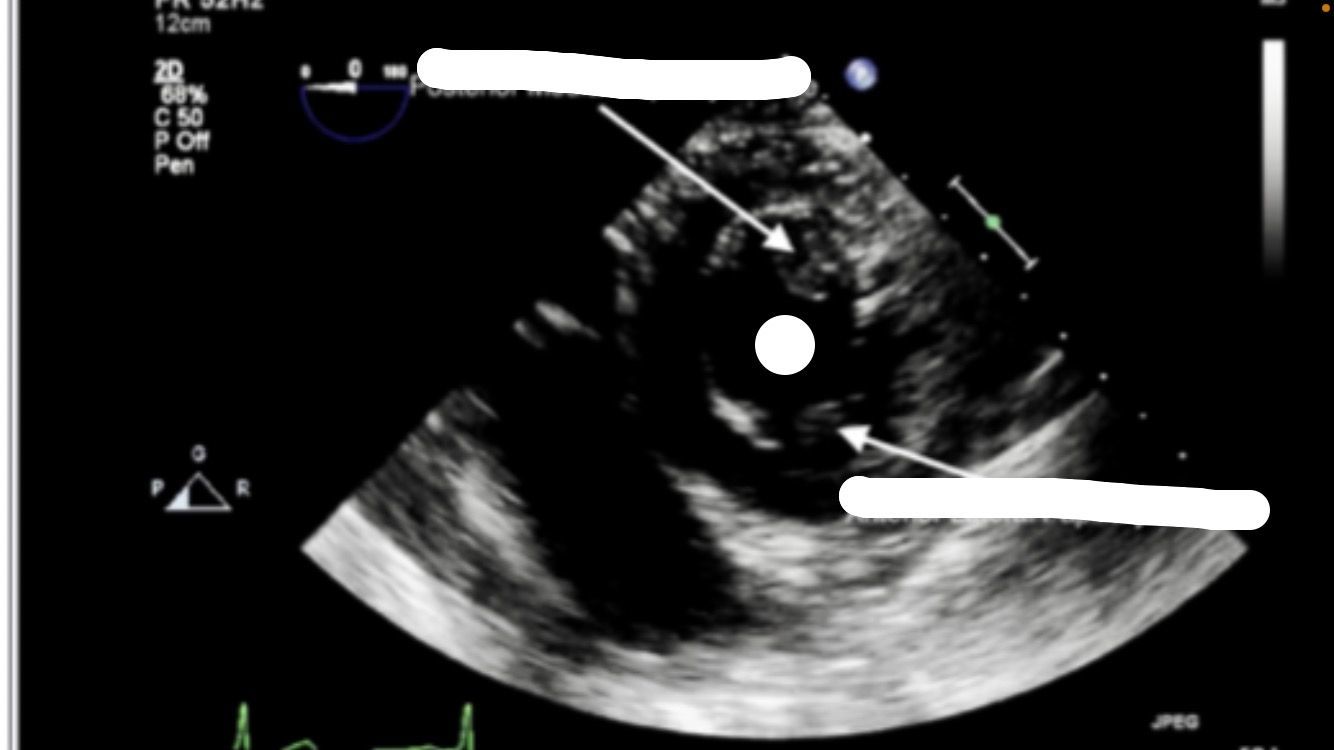

transgastric midpapillary SAX

transgastric mid SAX view